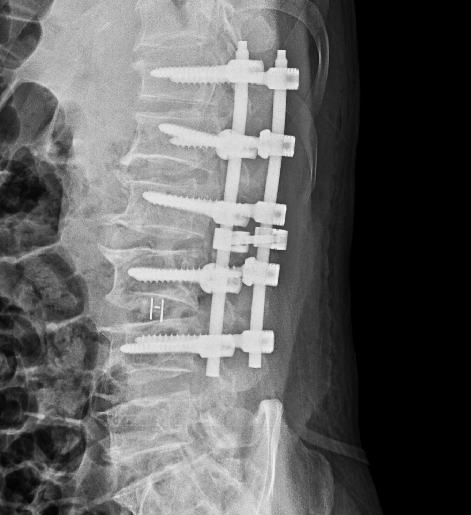

术后影像:

针对此病例诊断及治疗方案,周乙雄教授指导如下:

手术首先要考虑患者安全问题,此患者年龄偏大,心率慢(最慢38次/分),应安装起搏器,提高手术的安全度。

术中麻醉方式的选择也很重要,要选择对患者全身影响最小的麻醉方式,除腰麻外可考虑神经阻滞麻醉,必要的时候补充局部麻醉。

最后周教授表示本例病例手术做的很好,手术前对病例进行了各科室会诊,评估患者的心功能,这一点做的非常正确。

诊疗中应精准掌握手术适应症。此病例患者因外伤引起腰1、2椎体压缩骨折入院治疗,病例记载中患者有下腰部的退行性改变但没有明显椎管狭窄症状,因此手术适应症局限在腰1、2。

患者42岁尚年轻,没有明显椎管狭窄症状,将整个腰椎内固定是否范围过大。若患者高龄,下腰部有退行性改变并伴有椎管狭窄症状,可采用如此的手术操作方式,将腰3、4、5进行减压内固定。

因此医生应严格掌握手术适应症,要明确哪些手术可做,哪些手术不可做,哪些手术可做可不做,精准掌控手术适应症。